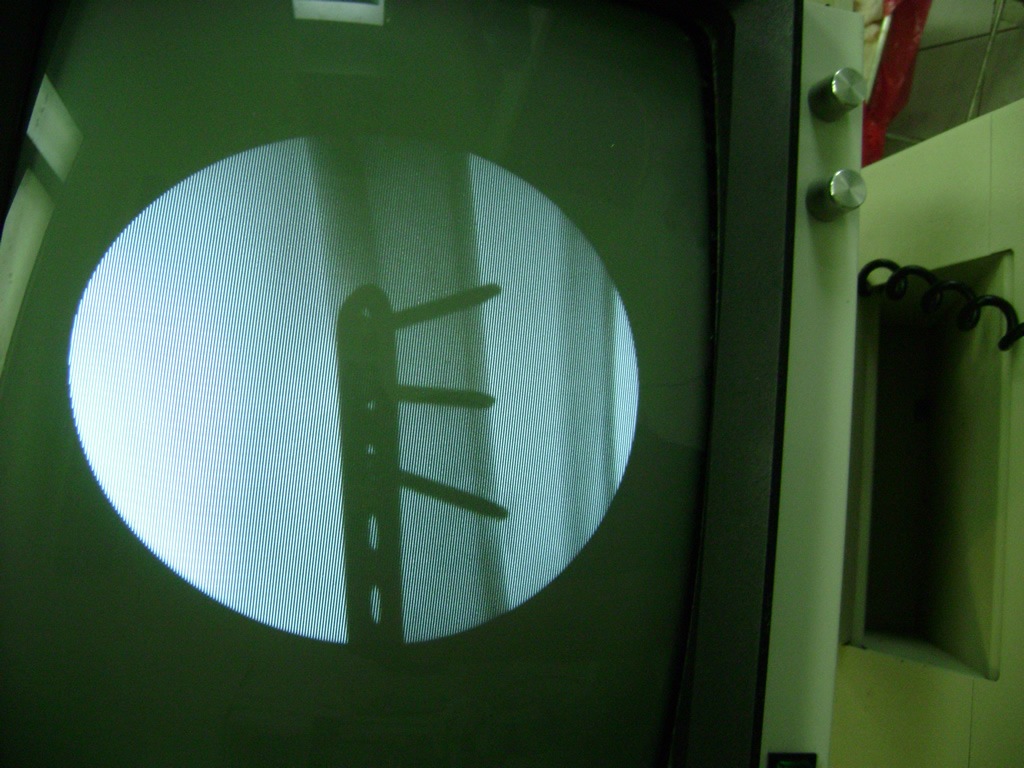

Cirugías de Codos - Perone y Tibia

Aunque cada uno de estos huesos puede fracturarse por separado, normalmente la rotura es una lesión que se produce de forma conjunta

Debido a la fina cobertura de piel que recubre la tibia y el peroné, las fracturas generalmente son abiertas, es decir, el hueso roto rasga la piel, atravesándola. Las fracturas de tibia y peroné generalmente se producen por un fuerte impacto o torsión.